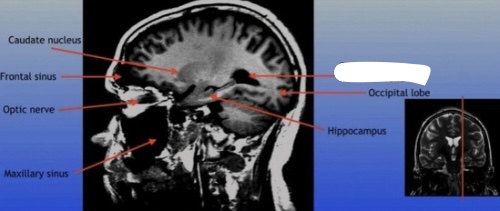

Caudate Nucleus

A C-shaped structure within the brain's basal ganglia, involved in various functions including motor control and learning.

Frontal Sinus

A paired cavity located within the frontal bone, above the eyes, that plays a role in sinus drainage and resonance of the voice.

Optic Nerve

The bundle of nerve fibers that transmits visual information from the retina to the brain. It plays a crucial role in the sense of sight.

Maxillary Sinus

A paired cavity located within the maxilla, situated below the eyes, that contributes to sinus drainage and helps lighten the weight of the skull.

Hippocampus

A critical region in the brain associated with memory formation and spatial navigation, located in the medial temporal lobe.